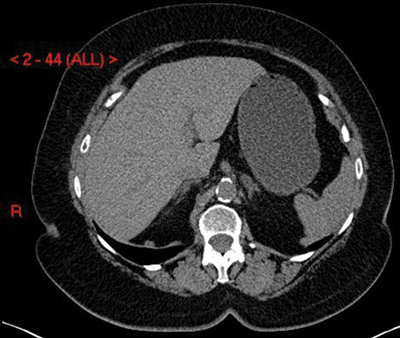

The two most common imaging modalities used to assess indeterminate adrenal lesions are multi-phase IV contrast-enhanced CT scanning and multi-sequence MRI scanning. Radiology departments vary on which method they choose depending on modality preference and capacity. If an adrenal lesion is detected incidentally on a CT scan, then it can often be classified as benign based on this initial scan. Eighty percent of adrenal adenomas have a high level of microscopic (intra-cytoplasmic) fat and will therefore have low Hounsfield units (HU). On an unenhanced CT scan, a lesion with an average HU <10 will have a sensitivity of 71% and a specificity of 98% for adenoma [4] (Figure 2). If the lesion has an average HU of >10 then adrenal-specific imaging will need to be performed to determine whether the lesion is a ‘lipid-poor’ adenoma or whether it is a malignant lesion.

Figure 2: Adenoma on unenhanced CT shown as a well-defined left adrenal nodule with HU <10.